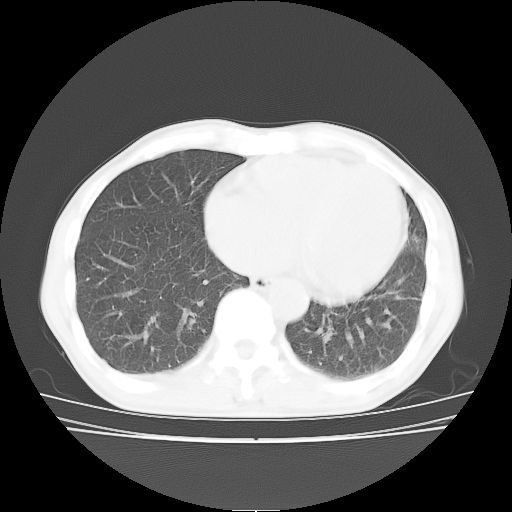

标题: CT25795:感冒后反复咳嗽两月余,痰中带血半月余。X诊断“肺 [打印本页]

标题: CT25795:感冒后反复咳嗽两月余,痰中带血半月余。X诊断“肺

1.双肺肺梗塞(理由:病灶呈三角形,与胸膜相连且局部胸膜肥厚,左心室增大)伴肺感染。

考虑两肺感染性病变,左肺上叶舌段肿瘤性病变待排;建议抗炎治疗后复查。